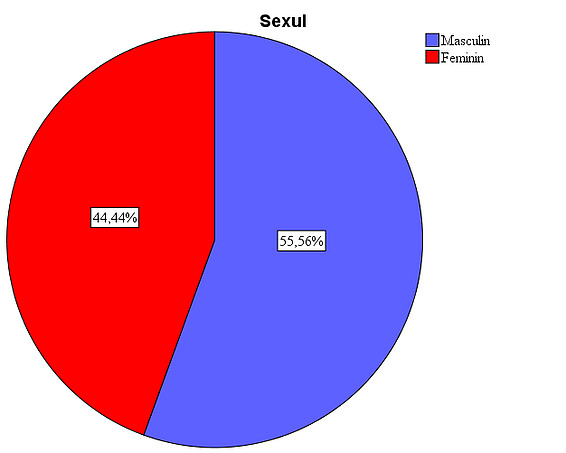

The studied sample includes subjects of both sexes, with males accounting for 55.6% and females accounting for 44.4%.

Figure 1: Gender distribution in the study. The presence of a larger number of male patients is due to the large number of eviscerations after ocular trauma, a pathology more frequently encountered in males (33 cases). The implant types were used in a relatively equal proportion: in 26.7% of patients the silicone implant was used, in 25.6% the synthetic hydroxyapatite implant, in 24.4% the acrylic implant, and in 23.3% the natural hydroxyapatite implant.

- The studied sample includes subjects of both sexes, with males accounting for 55.6%, while females accounting for 44.4%, explained by the high rate of ocular trauma in male patients